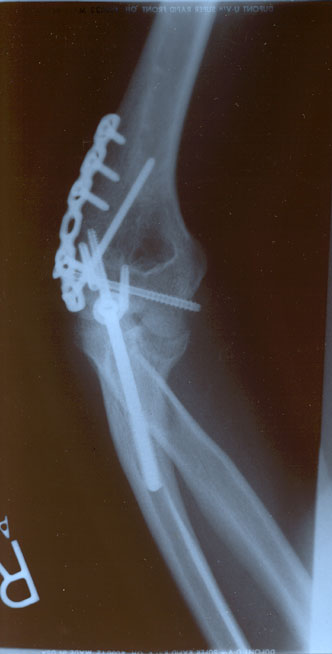

check out my new hardware.